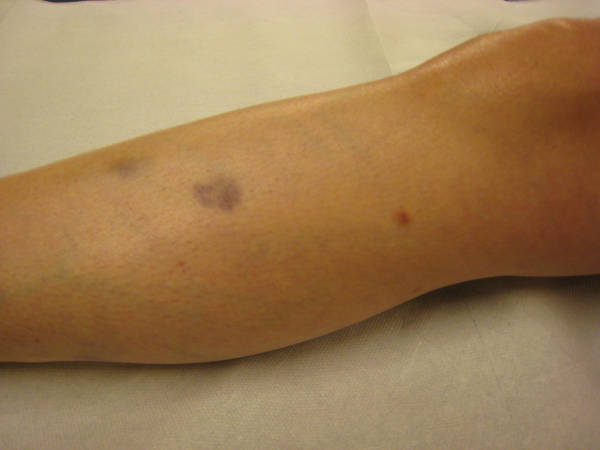

Dermatofibroma is a common cutaneous nodule of unknown etiology that occurs more often in women. Dermatofibroma frequently develops on the extremities (mostly the lower legs) and is usually asymptomatic, although pruritus and tenderness are not uncommon. The latter feature is seen in a sufficient number of patients to make dermatofibroma the most prevalent of all painful skin tumors. A number of well-described, histologic subtypes of dermatofibroma have been reported. Removal of the tumor is not necessary unless diagnostic uncertainty exists or particularly troubling symptoms are present.

Dermatofibromas typically arise slowly and most often occur as a solitary nodule on an extremity, particularly the lower leg, but any cutaneous site is possible. Several lesions may be present, but only rarely are multiple (ie, 15 or more) tumors found. This multiple variant is seen most frequently in the setting of autoimmune disease or altered immunity, such as systemic lupus erythematosus, Graves disease,10 , Down syndrome,11 , HIV infection, or leukemia and may be indicative of worsening immunoreactivity.

Typically, the clinical appearance of dermatofibroma is a solitary, 0.5- to 1-cm nodule. A sizable minority of patients may have several lesions, but rarely are more than 15 lesions present. The overlying skin can range from flesh to gray, yellow, orange, pink, red, purple, blue, brown, or black, or a combination of hues (see the image below). On palpation, the hard nodule may feel like a frozen pea or a small pebble fixed to the skin surface and is freely movable over the subcutis. Tenderness may be elicited with manipulation of the lesion.